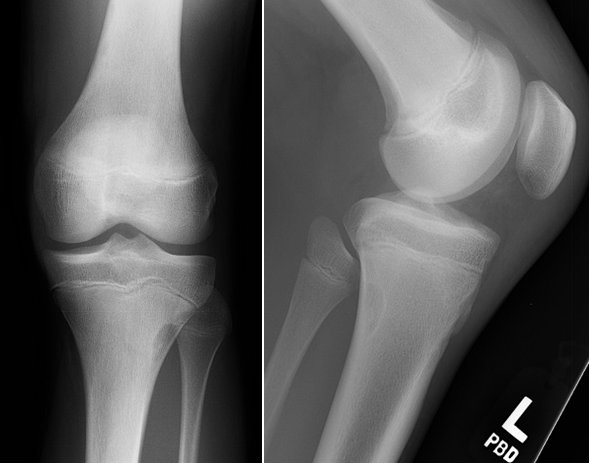

Learning Objectives: At the conclusion of the general orthopedic self-assessment exam physician assistants should be familiar with radiographic characteristics of benign and malignant bone tumors, be able to identify common benign bone tumors including enchondroma, unicameral bone cyst, nonossifying fibroma, osteoid osteoma, aneurismal bone cyst, giant cell tumor, and osteochondroma, be able to identify common malignant bone tumors including osteosarcoma, chondrosarcoma, and Ewing’s sarcoma, and be able to identify and understand treatment of pathological fractures from metastatic disease.